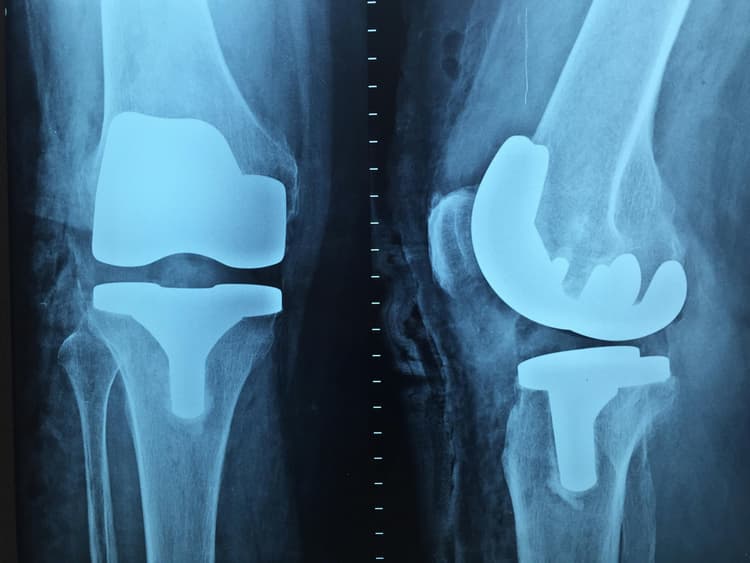

Osteoartrit, romatoid artrit ve avasküler nekroz gibi ileri evre eklem hastalıklarında total diz, kalça veya omuz protezi uygulaması gerekebilir. Artroplasti alanında deneyimli uzmanlar; minimal invazif teknikler, bilgisayar destekli navigasyon sistemleri ve robotik cerrahi kullanımıyla daha hassas ve uzun ömürlü protez yerleşimleri gerçekleştirebilir. Türkiye'de yıllık 60.000'in üzerinde diz ve kalça protezi ameliyatı yapılmaktadır.